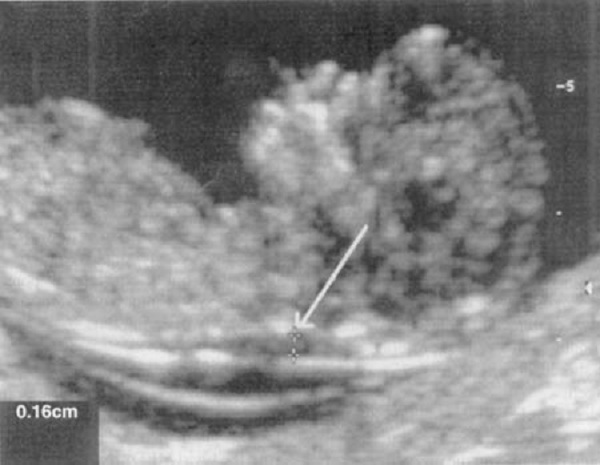

7. On the first trimester of the pregnancy the ultrasound has been made. Which of the following is associated with this condition?

A. Increased of alpha protein

B. Decreased of alpha protein

C. Increased estriol

D. Decreased ß-hCG

- The correct answer is B. The Down syndrome is suspected because the ultrasound shows increased nuchal translucency. According the pregnancy screen of women with suspected fetus with Down syndrome shown decreased alpha protein.